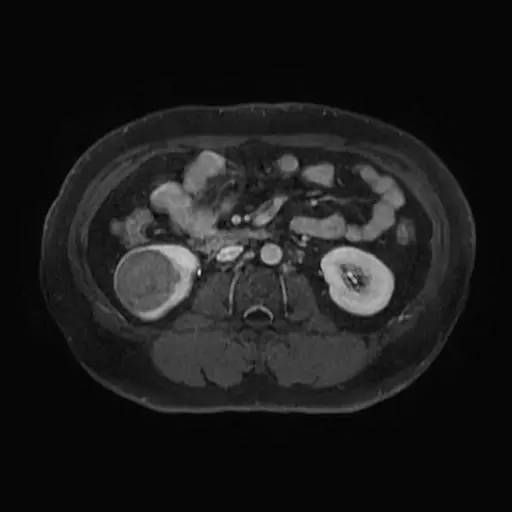

右肾中下部见类圆形约52*49*59毫米类圆形短和稍长T1、短和长T2异常信号肿块,可见假包膜,DWI呈晕环结节状稍高和稍低信号,反相位图像病变信号未见异常减低;皮质期病变未见异常强化,髓质期及延迟期持续轻度强化;病变内小部分区域未见强化。所见肝胆、胰腺、脾脏及双侧肾上腺未见异常,肝门、肾门及所见腹膜后未见异常肿大淋巴结影。

影像诊断:右肾中下部少血供肿块伴出血、坏死和囊变,考虑:恶性肿瘤,以肾癌(非透明细胞癌)可能性最大,不能完全除外表现不典型的血管平滑肌脂肪瘤。